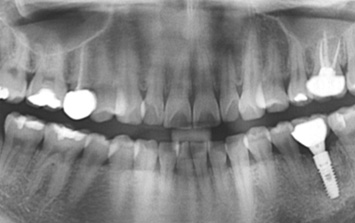

왼쪽 어금니 상실로 내원한 환자분. 위 턱뼈의 경우 아래턱뼈보다 얇고 상악동 있어 임플란트를 실패할 가능성이 높습니다.

턱뼈의 해부학적 구조를 충분히 고려한 상악동 뼈이식 후 임플란트를 식립하였습니다.